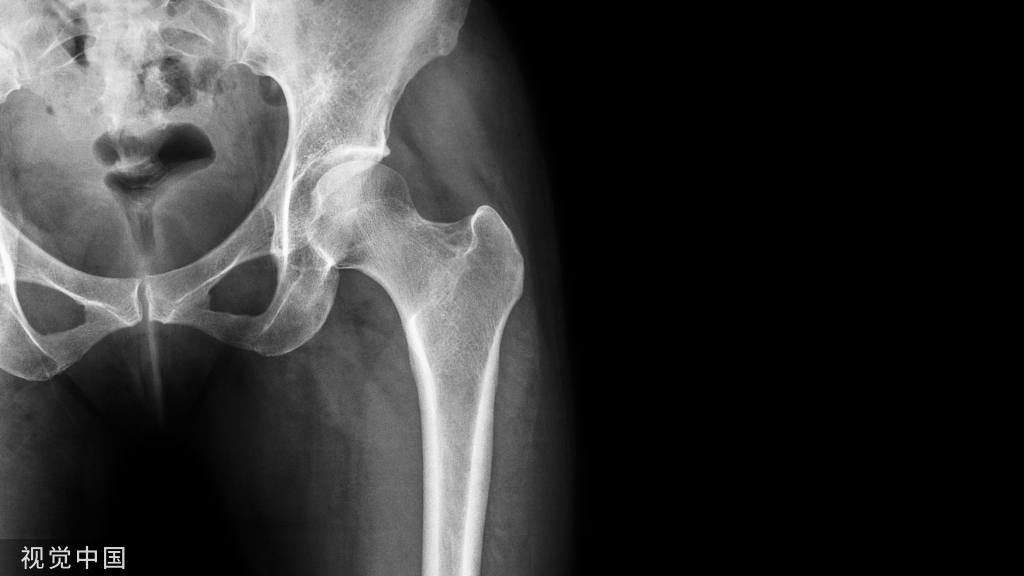

伸直型桡骨远端骨折(Colles骨折):多为腕关节节处于背伸位、手掌着地、前臂旋前时受伤。伤后局部疼痛、肿胀、可出现典型畸形姿势,即侧面看呈“银叉”畸形正面看 呈“刺刀样”畸形。局部压痛明显,腕关节活动障碍。可同时伴有下尺桡关节脱位及尺骨茎突骨折。

Colles骨折伤后局部疼痛、肿胀、压痛明显,腕关节活动障碍。X线拍片可见骨折远端向桡、背侧移位,近端向掌侧移位,因此表现出典型的畸形体征。